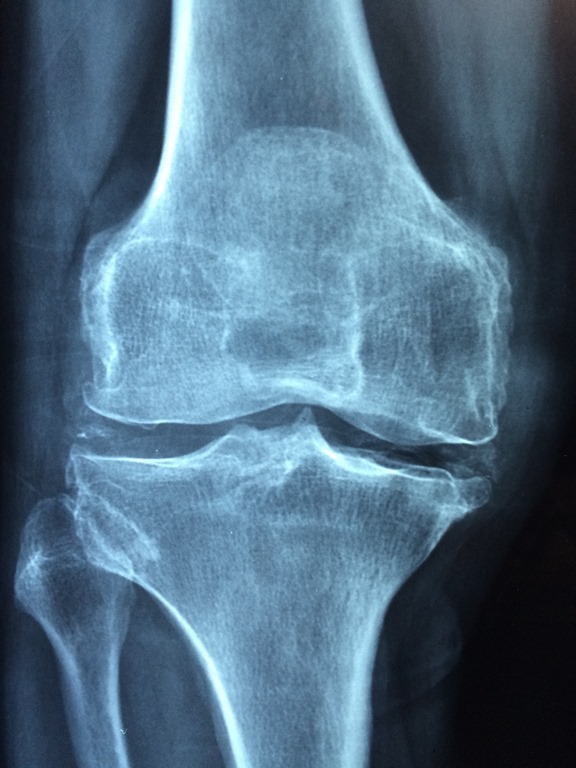

El diagnóstico de una meniscopatía es clave para tratarlo. Se confirma mediante un examen físico detallado y una resonancia magnética. Una vez identificada la lesión, la intervención quirúrgica puede ser necesaria, especialmente si el dolor y las limitaciones funcionales persisten.

Actualmente, la cirugía de menisco se realiza mayoritariamente con técnicas artroscópicas. Este procedimiento mínimamente invasivo permite reparar o extirpar el tejido dañado a través de pequeñas incisiones. “La artroscopia reduce significativamente los riesgos asociados a las cirugías tradicionales y permite una recuperación más rápida. En la mayoría de los casos, el paciente puede apoyar la pierna operada de inmediato y retomar sus actividades cotidianas en pocos días”, explica Fernando Bascuñán, traumatólogo de Clínica Miguel Claro.